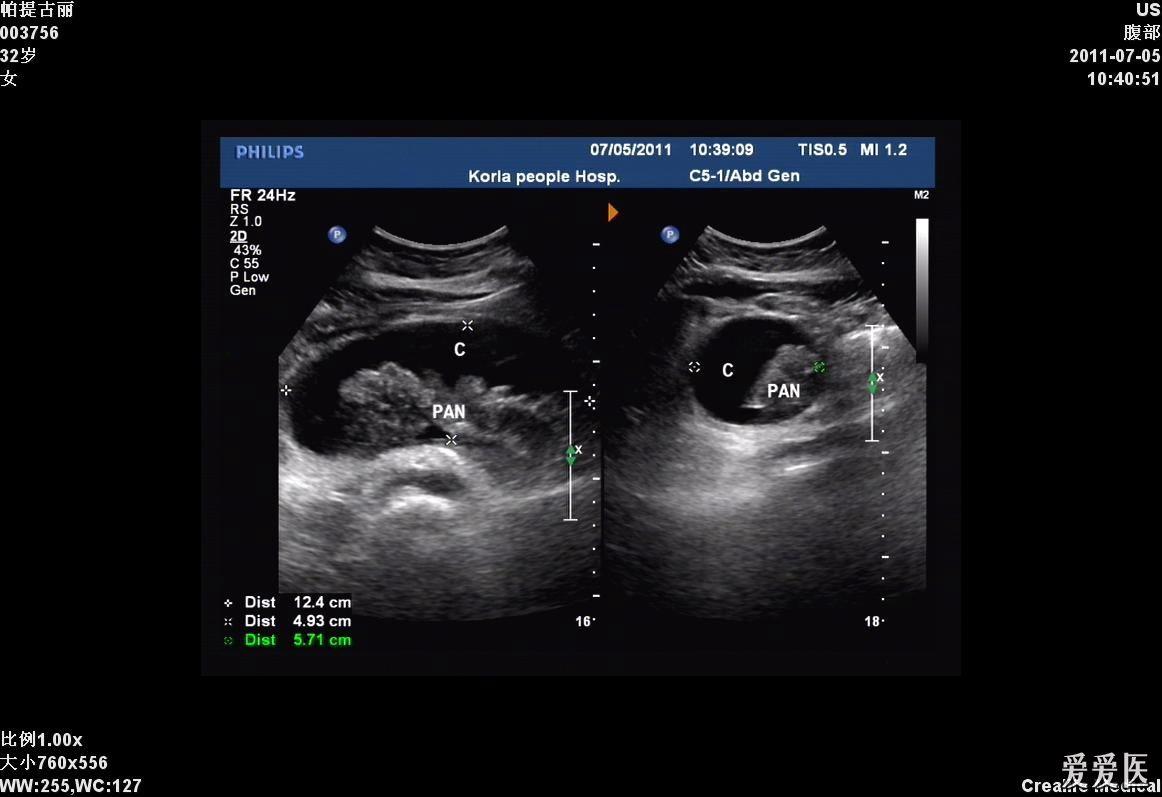

结石性胰腺炎合并胰腺假性囊肿形成